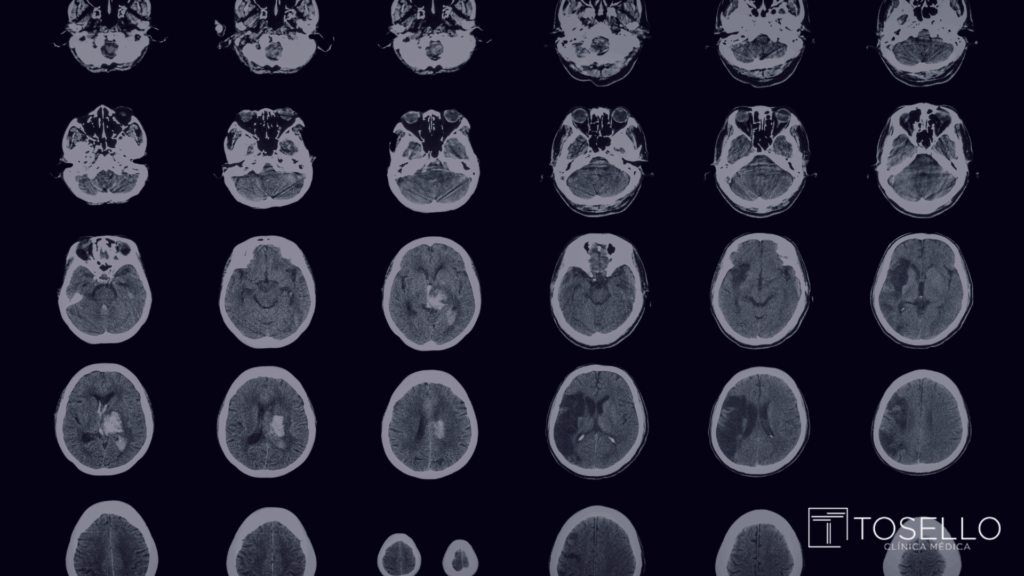

O acidente vascular cerebral (AVC) é uma das principais causas de morte e incapacidade no mundo. Dentro dele, o AVC isquêmico representa cerca de 85% dos casos, sendo provocado por uma obstrução no fluxo sanguíneo cerebral. Mas você sabe quais são os sinais de alerta e como prevenir esse problema?

O AVC isquêmico ocorre quando um coágulo ou placa de gordura bloqueia a passagem de sangue em um vaso do cérebro. Isso impede que o oxigênio chegue a determinadas áreas, causando a morte das células cerebrais em poucos minutos. É uma emergência médica que exige atendimento imediato.